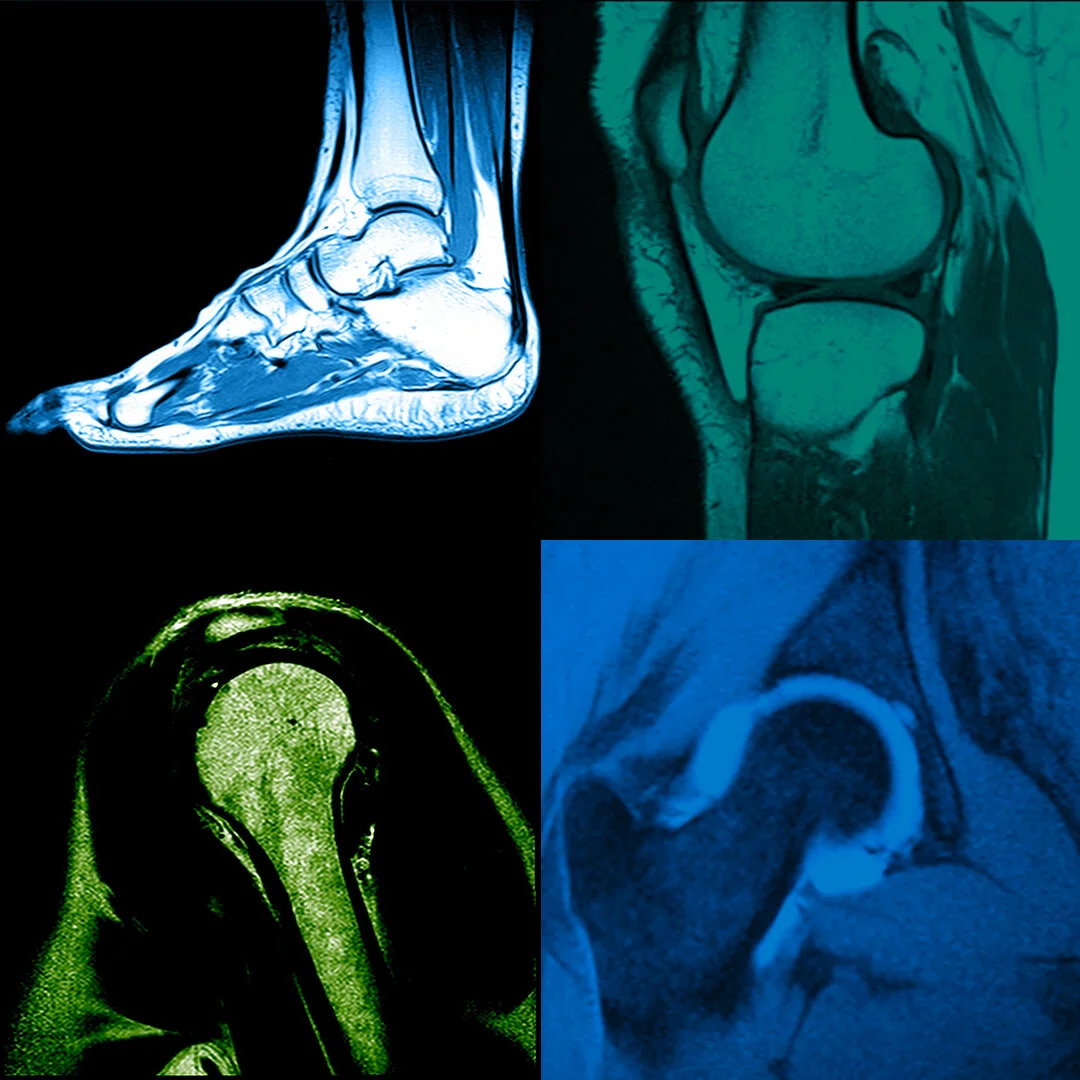

Pain in your joints, muscles, or back often needs more than a basic scan to understand the cause. Our Musculoskeletal MRI in Houston TX provides clear, detailed images of ligaments, tendons, cartilage, and muscles, helping your doctor identify injuries, inflammation, or structural issues with confidence. It is often recommended when symptoms continue or when a more detailed view is needed for proper diagnosis and treatment planning. We also serve patients needing a Musculoskeletal MRI in Richmond TX, offering the same level of precision, comfort, and reliable imaging experience.

At Maximum Resolution Imaging Center, Musculoskeletal MRI in Houston TX is used to examine joints, muscles, ligaments, tendons, and cartilage in detail. It is often recommended for ongoing pain, limited motion, sports injuries, or when earlier imaging does not provide enough clarity. This scan helps identify soft tissue injuries, joint damage, or inflammation so your provider can better understand the cause. Patients coming in for a Musculoskeletal MRI in Richmond TX can expect the same level of detailed imaging and attention.

Every Musculoskeletal MRI Scan is performed with a focus on clarity, consistency, and patient comfort. Our team follows proper imaging steps to ensure accurate results that are easy for your provider to review. When needed, 3T MRI for Musculoskeletal Imaging is used to capture higher detail for smaller or complex areas. Whether you are visiting for a Musculoskeletal MRI in Houston TX or from Richmond, the goal stays simple. Clear imaging that supports accurate diagnosis without making the process complicated.